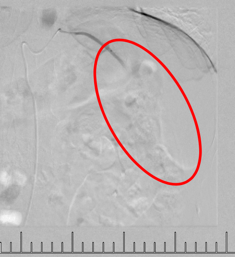

灌注藥物及栓塞后“烏云”消失

肋間動(dòng)脈阻斷營養(yǎng)來源